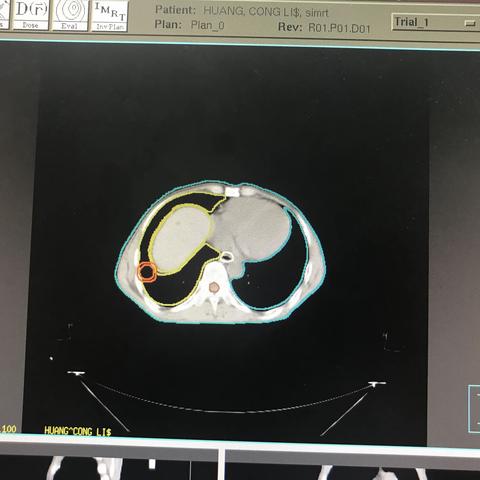

胃癌肝多发转移,SBRT,4D_CT,腹部压迫,单次1400CGYx3次,2个病灶!肝脏最大剂量20GY,V10小于50%!